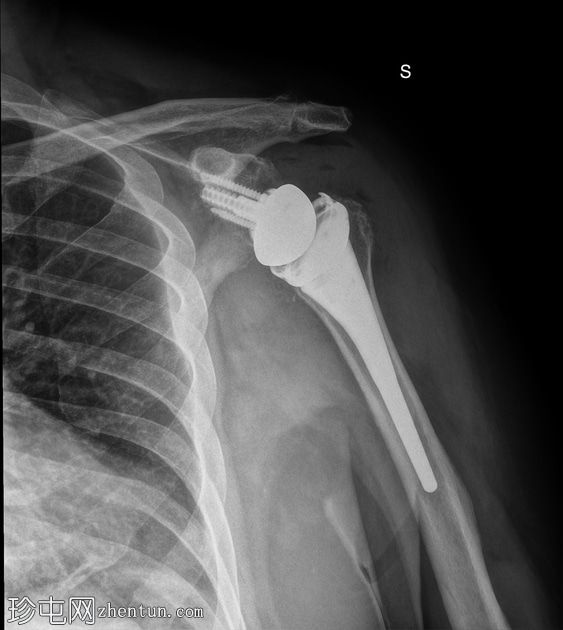

4.jpg

正面 - 外旋

全肩关节置换术后肱骨假体前脱位,伴假体分离。

目前,治疗全肩关节置换术 (RTSA) 脱位的策略尚不明确。闭合复位治疗肩关节脱位(RTSA)的疗效有限,而手术翻修可能需要多次干预才能达到稳定。增加肱骨长度和盂肱骨偏心距的翻修治疗可获得更高的成功率,这表明降低软组织张力是治疗肩关节脱位的关键因素。